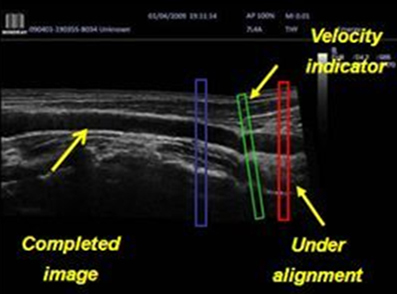

iScape (панорамная визуализация в реальном времени)

Детализированное и расширенное представление анатомической структуры посредством панорамной визуализации, дополненной индикатором скорости и функцией прямого или обратного сканирования. В результате процесс сканирования становится более легким, последовательным и управляемым.